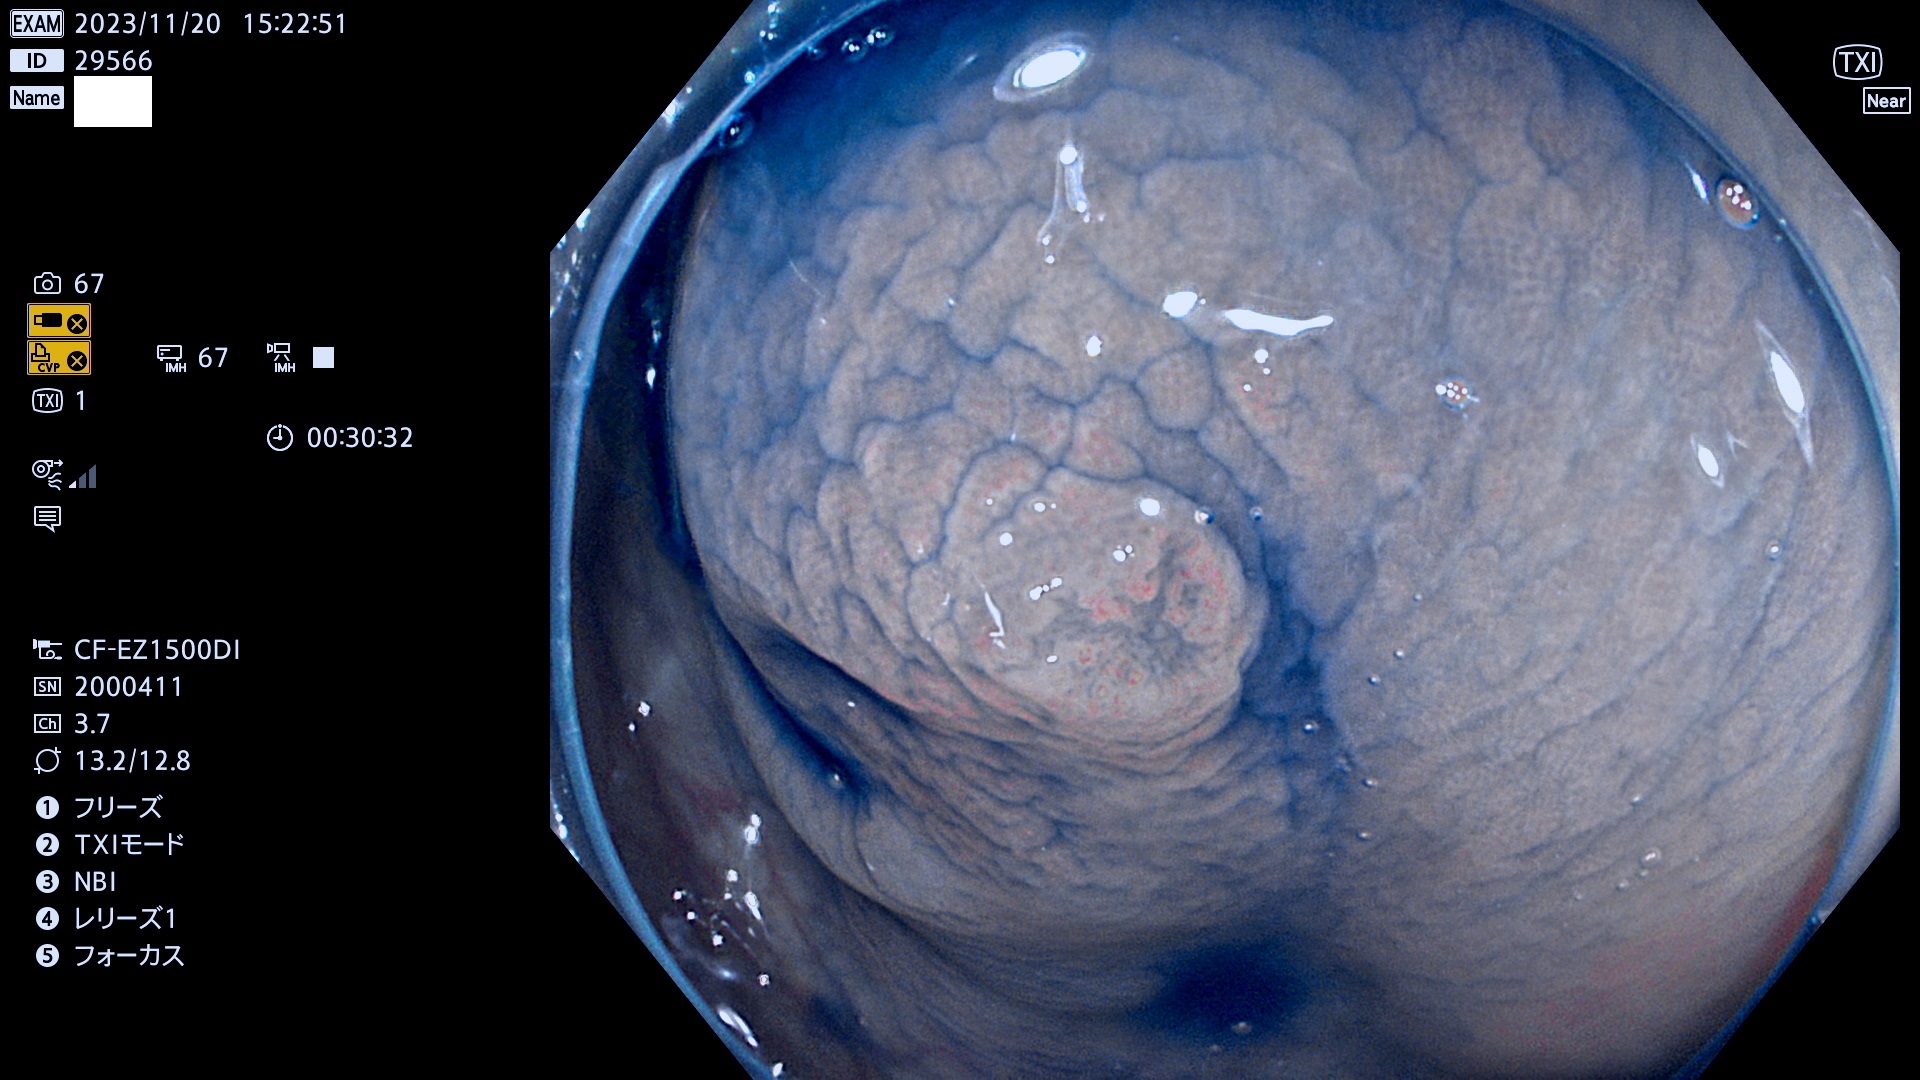

表面型腺腫(Flat Adenoma)の中で、完全に平坦な物をUb、陥凹している物をUcと呼びます。平坦隆起型(Ua)よりも、発見が難しく危険な病変です。このタイプは「内視鏡後・大腸癌の重要犯人」であり、この発見率は「腺腫発見率」よりも、重要な意味があります。

専門的)何故、陥凹していると危険? 癌遺伝子の変異が蓄積すると細胞分裂が盛んになり隆起するのでは?と通常は思われるでしょう。しかし実際は逆です。これは2022年の記事にある「細胞はストレスに直面したら細胞分裂を止める(細胞老化に入り休眠する)という生命の基本的現象」によるものです(Oncogene Stress)。細胞老化を起こすのが癌抑制遺伝子で、この安全装置(ブレーキ)が壊れると癌になります(休眠からの覚醒)。ですから陥凹は「まだ癌では無いが癌化の直前」を意味します。特に「小サイズなのに陥凹している」病変は短期間に腫瘍進化(⇒2021年記事)が起きたことを意味します(=ゲノム不安定性

毎週の検査(木・金・土・日)に発見されたUb、Uc型・腺腫を、その週の日曜の夜にUPし1週間、提示します。

抽出の対象期間 2023年11月16日(木)〜11月20(日)の5日間(60件の検査)11件